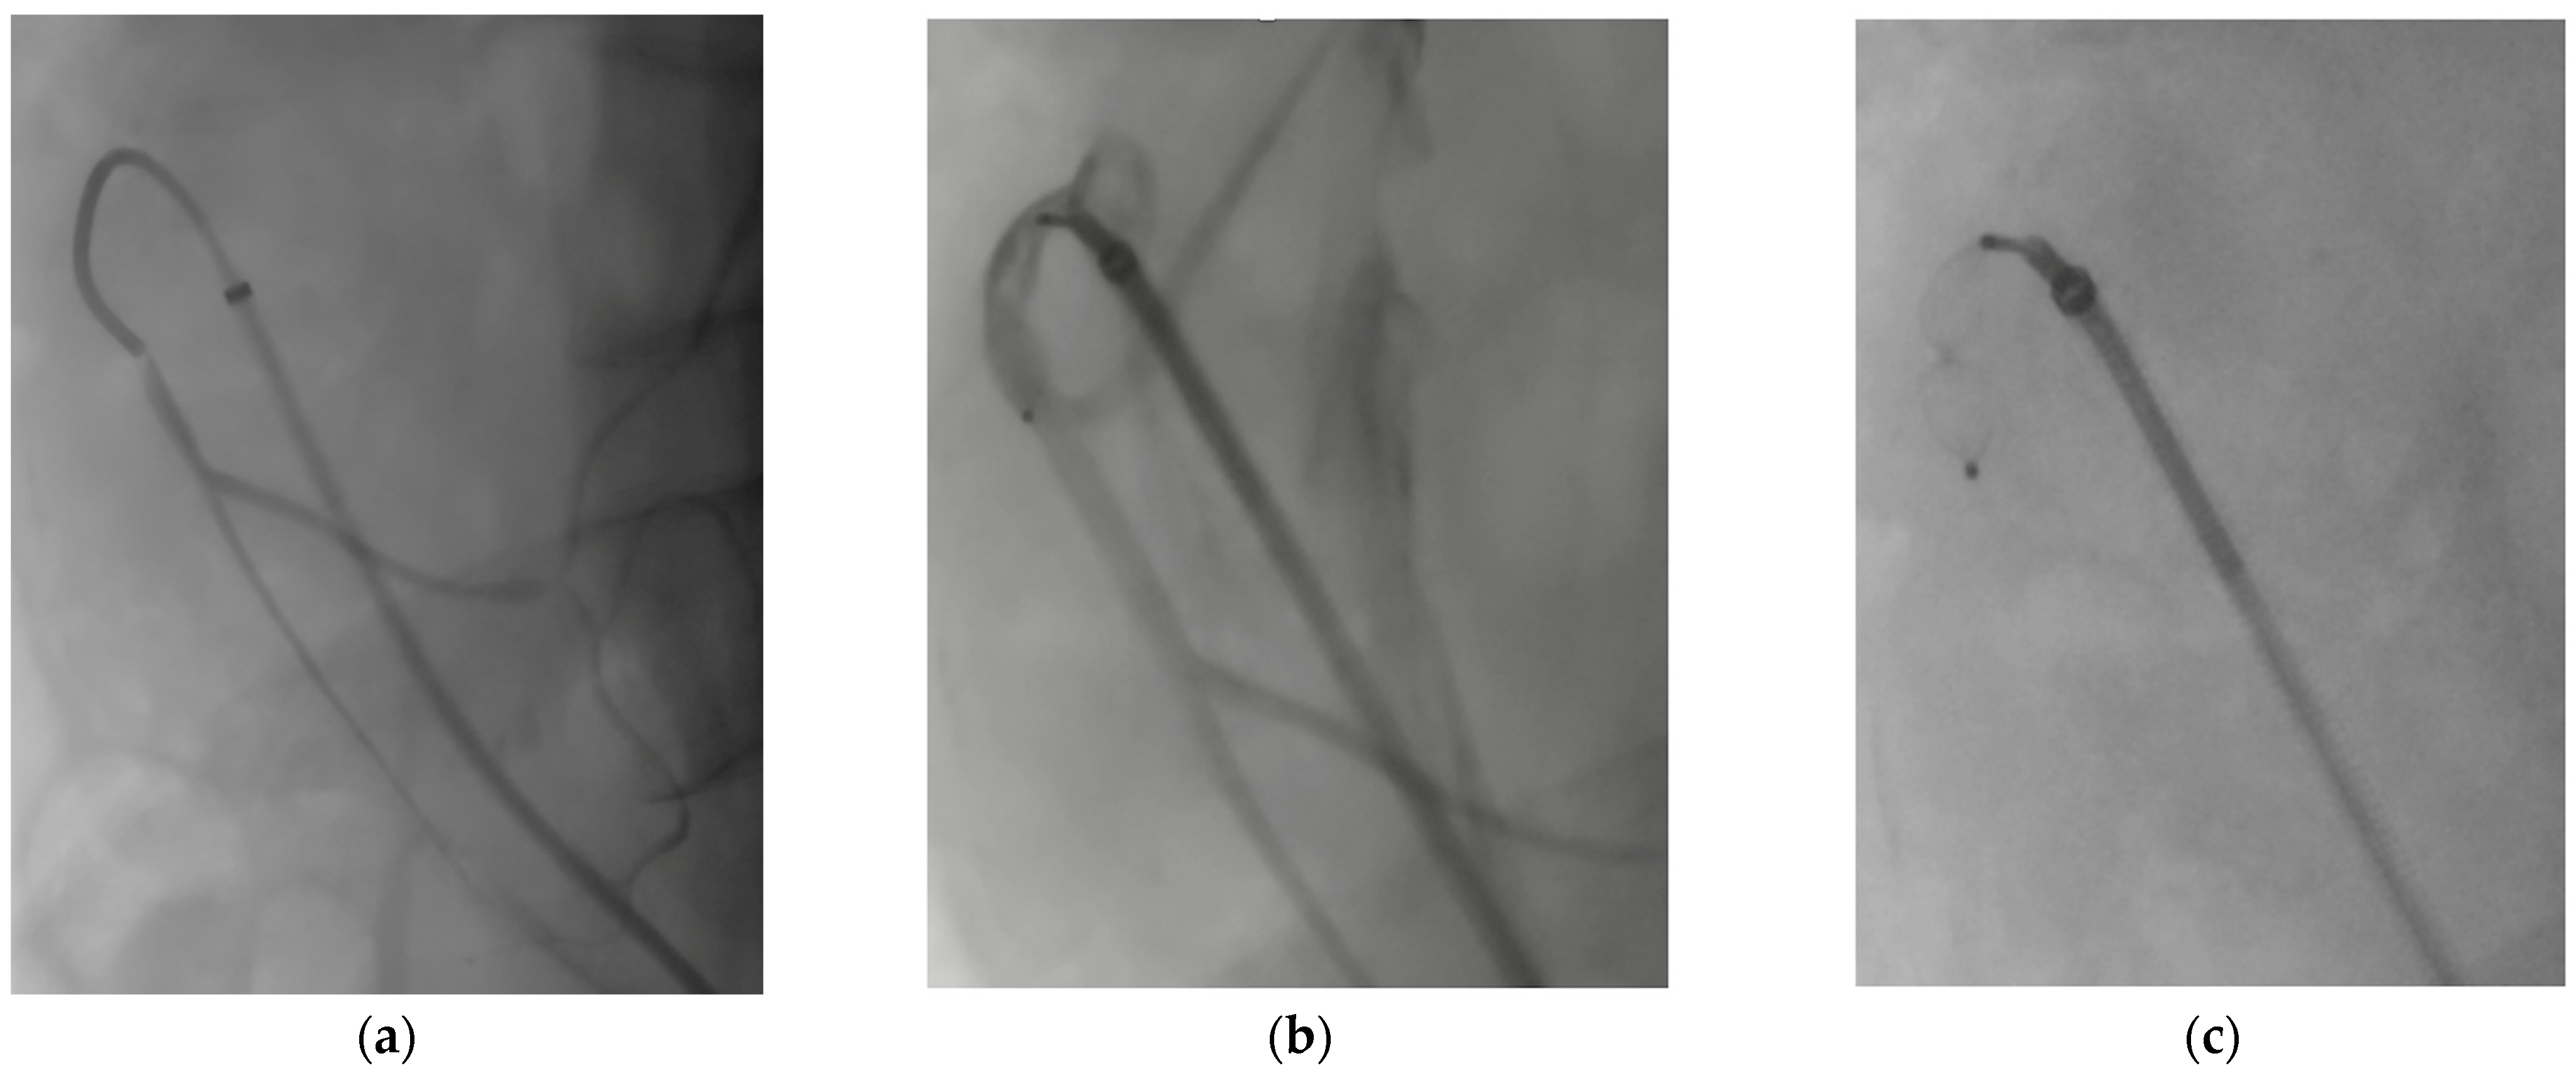

- As a modification of the original technique from Ferreira et al. [44], Tenorio et al. [45] suggested that branch elongation with a balloon-expandable stent before plug release should be the preferred choice in order to extend the sealing zone; the directional branch should be extended at least 20 mm beyond the branch cuff, and the plug should be released entirely within the stent, with no lobes protruding on the outside (Figure 6a). This configuration would limit any plug migration caused by short landing length inside the branch cuff.

- Alternatively, the “dog bone” technique [46] consists of deploying a balloon-expandable stent-graft inside the branch, sizing it 2 mm larger than the branch itself. It should be inflated to 8 mm, and the proximal and distal portions of the stent should be flared with a larger balloon (4 mm more than the branch diameter). An AVP II should then be released at the beginning of the narrowed part, thus creating a bottleneck effect.

- The MVP-7Q (MVP, Medtronic, Minneapolis, MN, USA) has also been used to occlude branches, with promising results in terms of early success and avoiding the use of a further bridging stent–graft, thus reducing overall procedural costs and possibly operating time [47] (Figure 6b). Aside from the economic and technical aspects, the MVP PTFE membrane design guarantees immediate vessel occlusion, which is of paramount importance in symptomatic/ruptured aneurysms, as opposed to the AVP II design which needs time to achieve complete branch thrombosis.